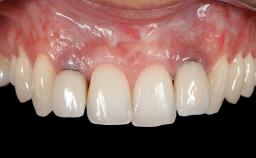

In this case, Shakeel Shahdad employs a two-layer matrix to repair a soft-tissue defect in a post-extraction healed site prior to implant placement with simultaneous guided bone regeneration. This approach resulted in a gain of keratinized peri-implant mucosa with optimal shade and texture. Soft-tissue defects are often encountered prior to implant placement and may result in deficient attached keratinized mucosa, which unless corrected will yield less than ideal esthetic outcomes. The presence of keratinized mucosa has been proposed as one of the prognostic factors for the survival of dental implants (Adell and coworkers 1986) with reported greater reductions in gingival and plaque indices after increasing the width of keratinized mucosa by soft-tissue augmentation (Giannobile and coworkers 2018; Thoma and coworkers 2018).